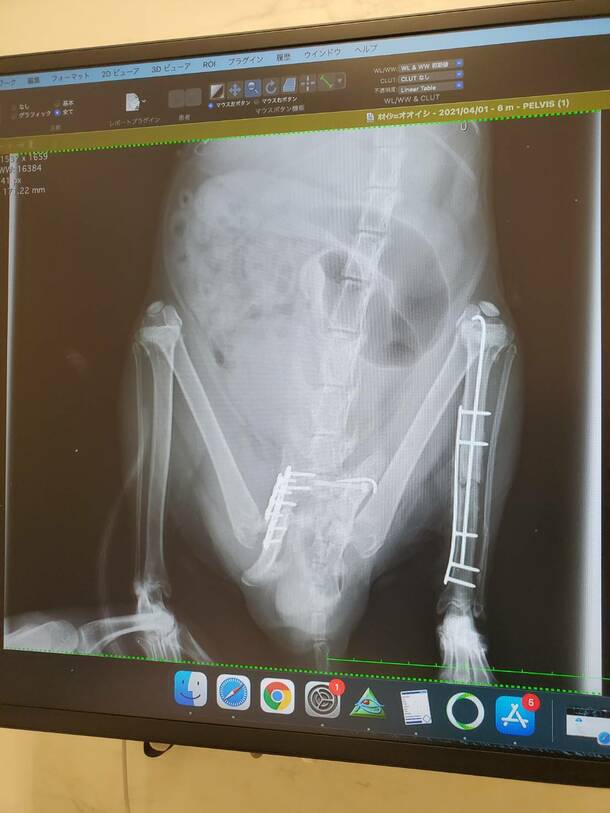

退院後3日目検査

プレートのずれもなく今のところ問題なし😀